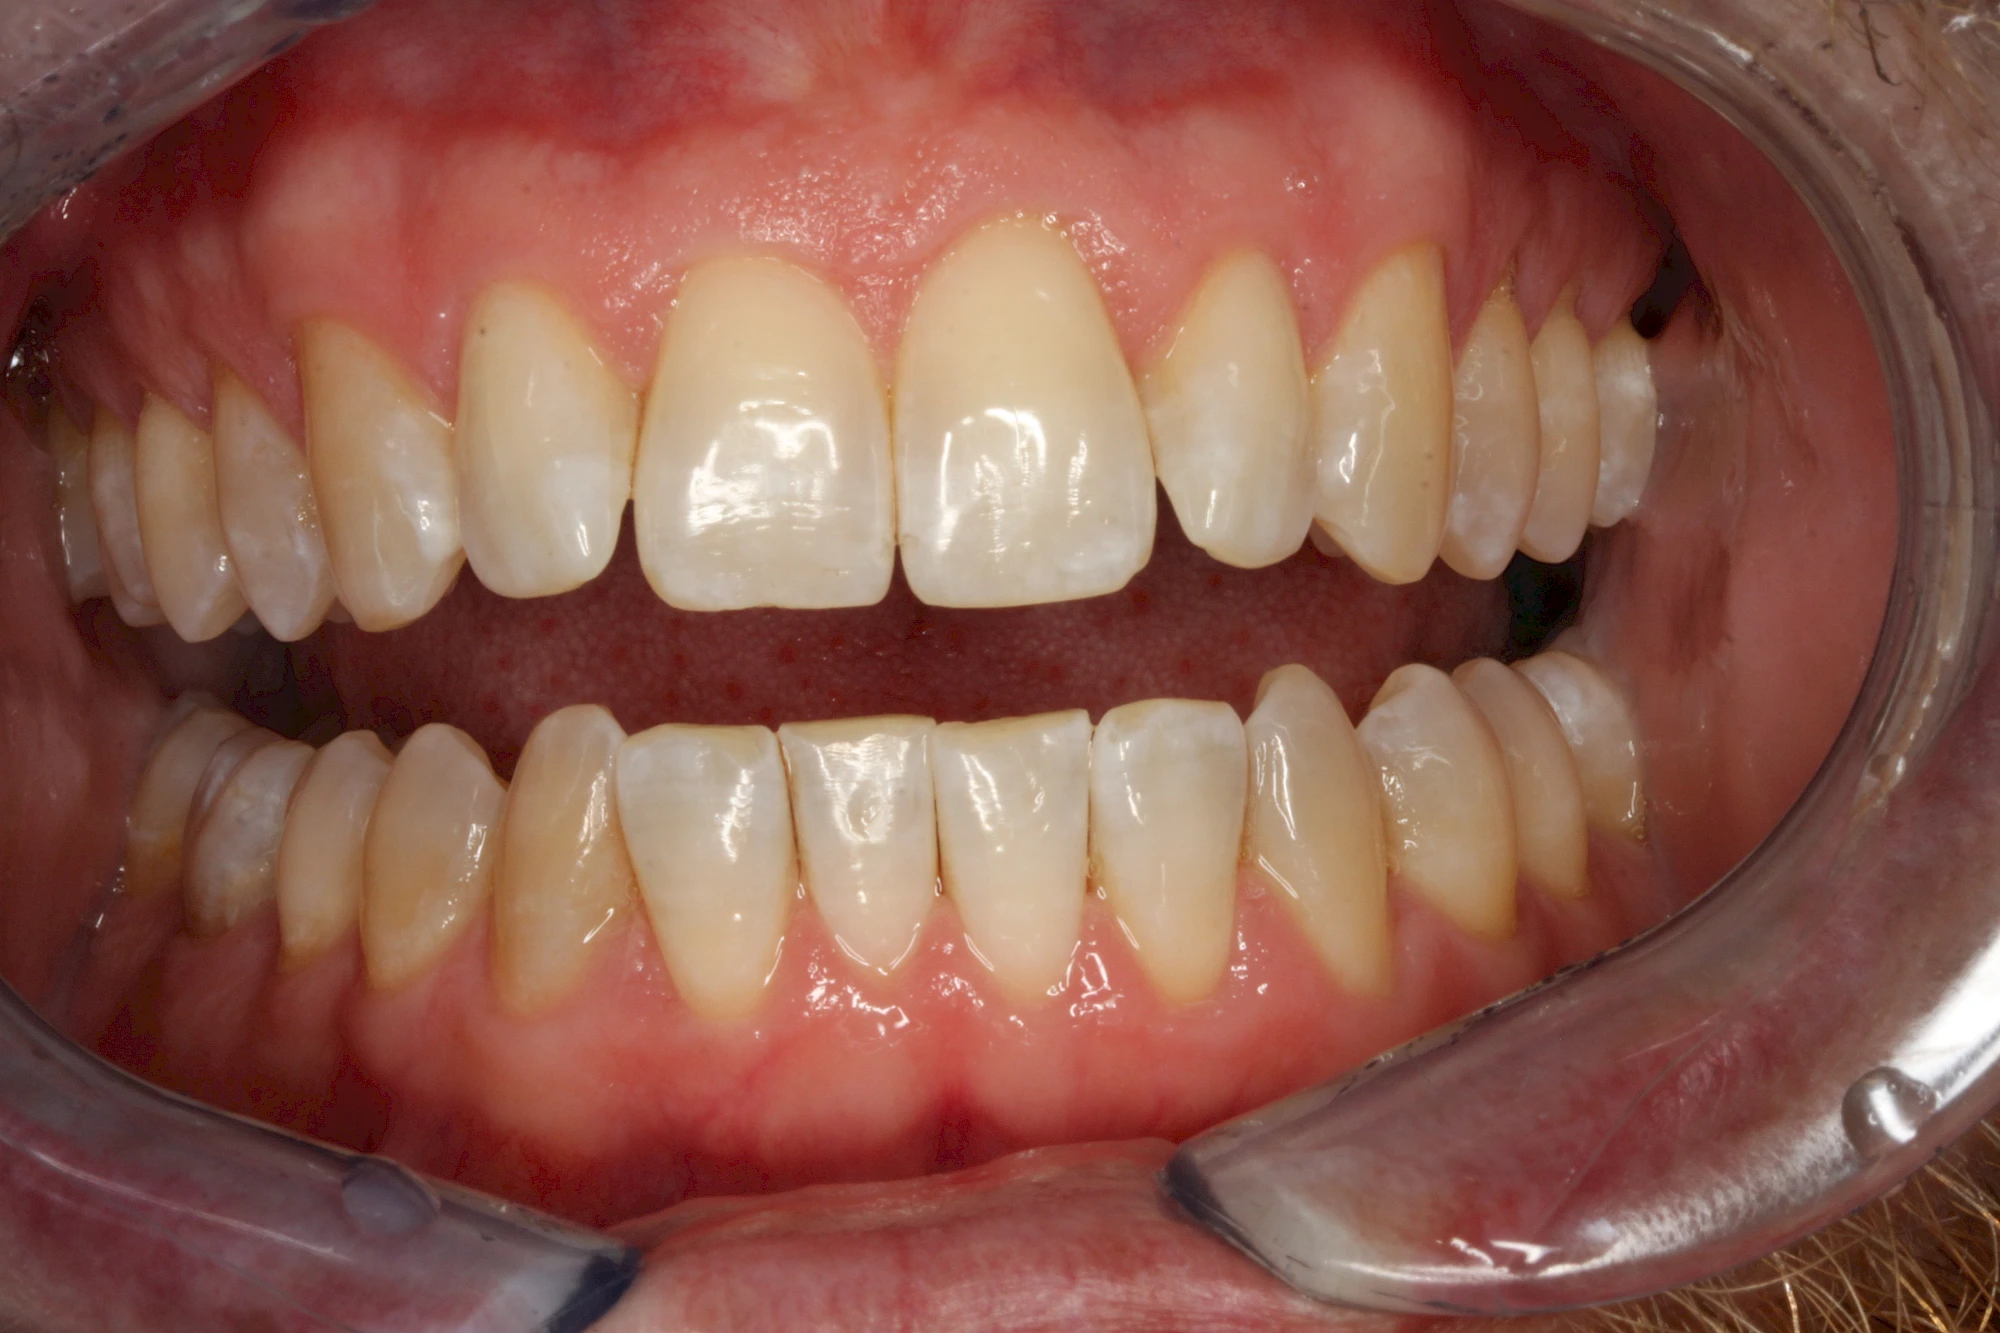

Von außen (exogen) eher dunkel gefärbt und meist mehrere Zähne betroffen:

- Genußmittel (Tee, Kaffee, Rauchen)

- Medikamente (z. B. Eisen)